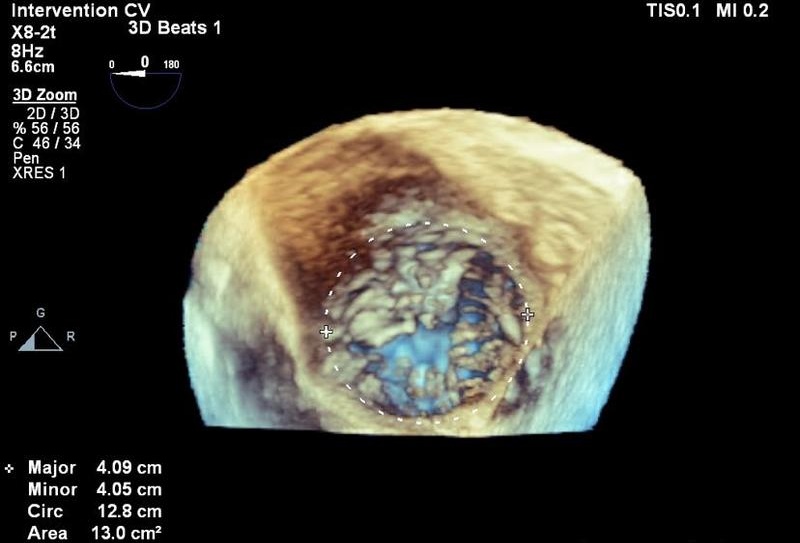

一根经颈内静脉输送的特制导管,将精巧的K‑Clip®夹合装置准确送入患者心脏。在超声实时引导下,手术团队通过微小的血管通路,对患者扩大的三尖瓣环进行精准修复。这是仁济医院宝山分院成功开展的K‑Clip®经导管三尖瓣环成形术,为一位极重度三尖瓣反流患者实施微创治疗的真实场景。

术后评估显示,患者三尖瓣反流程度从术前的极重度降至中度,临床症状得到显著改善。李女士目前也已在康复中。